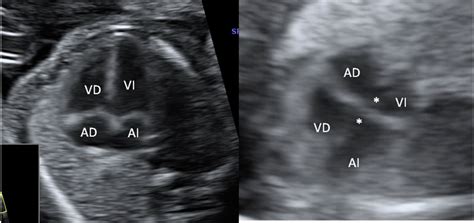

Mediante la ecocardiografía fetal, se valoran aproximadamente 250 cardiopatías congénitas al año. Esta técnica permite evaluar la estructura y el funcionamiento del corazón, detectando posibles problemas en su formación o ritmo cardiaco. El diagnóstico precoz de estas afecciones, como demuestran estudios científicos, mejora significativamente el pronóstico del feto, posibilitando tratamientos adaptados durante la gestación y asegurando que el parto tenga lugar en un centro especializado para una evolución óptima.